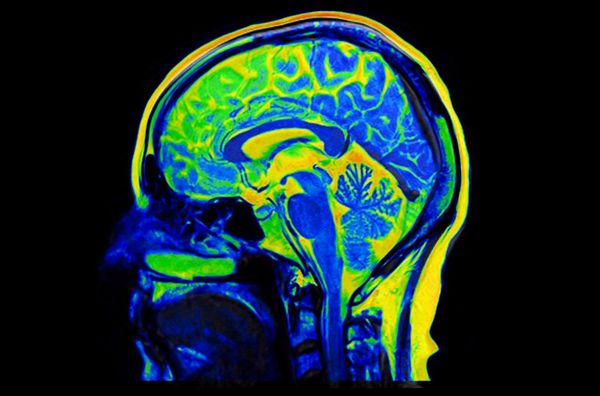

Schädliche Stoffe werden in Körperzellen abgebaut und wiederverwertet. Wiener Forschende ergründen, warum das bei Krankheiten wie Alzheimer oder Parkinson versagt Mäuse bekommen normalerweise kein Alzheimer...weiterlesen »